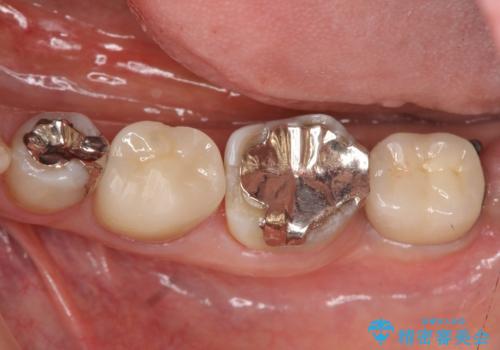

良好なインプラントの植立を行うためには、十分な骨量があることが必須条件です。

術前、歯の破折により大きな骨の吸収が認められていたため骨量を十分に回復するために抜歯と同時に歯槽堤保存術を行い十分な骨量の回復をすることができました。